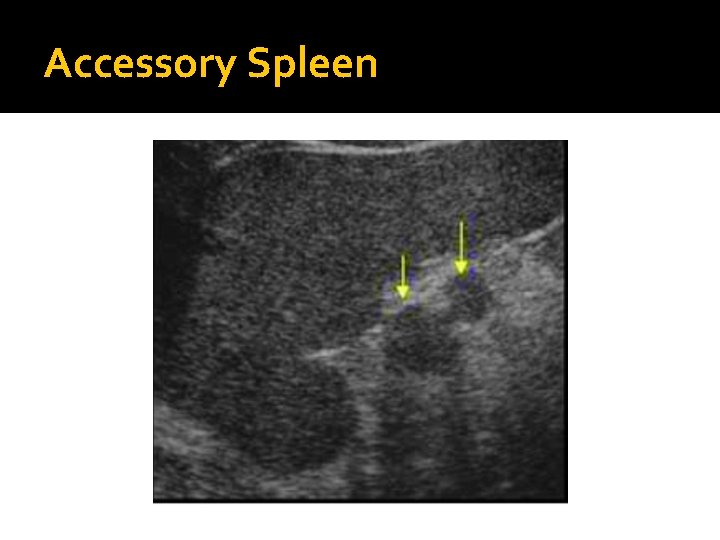

Accessory Spleen �Developed in embryology, an accessory spleen is a small nodule of splenic tissue found apart form the main body of the spleen. �Found in approximately 10% of the population, it is most commonly found in the splenic hilum and adjacent to the tail of the pancreas. �May be mistaken for Splenomegaly or a focal mass.

�An accessory spleen is a normal variant that is commonly found. It may be confused with enlarged lymph nodes around the spleen, or a mass in the tail of the pancreas. �The majority of accessory spleens are easy to recognize sonographically as small rounded masses, less than 5 cm in diameter. They are located near the splenic hilum and have identical echogenicity to the adjacent spleen.

Accessory Spleen